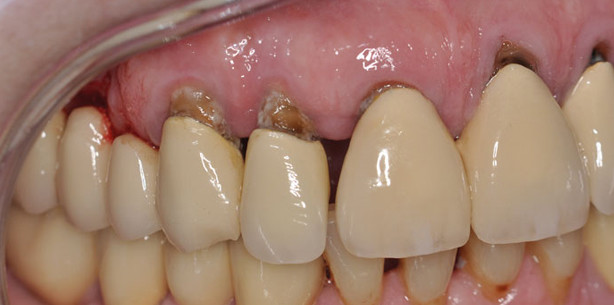

Zu den von älteren Patienten regelmäßig eingenommenen Medikamenten, die eine Mundtrockenheit verursachen können, gehören kardiovaskuläre Medikamente (Antihypertensiva, Diuretika, Kalziumkanalblocker, Diuretika), trizyklische Antidepressiva, Hypnotika und Sedativa, Chemotherapeutika/Zytostatika, Antihistaminika und Antiparkinsonmittel.5 Durch die fehlende protektive Wirkung des Speichels entwickeln sich oft bakterielle, virale und mykotische Schleimhautinfektionen mit einer gesteigerten Prävalenz für Gingivitiden und Parodontitiden.14 Darüber hinaus sind infolge einer medikamentös verursachten Hyposalivation ältere Menschen stark gefährdet für die Entstehung kariöser Läsionen an Glattflächen, Füllungs- und Kronenrändern sowie im Bereich von Wurzeloberflächen (Abb. 2).